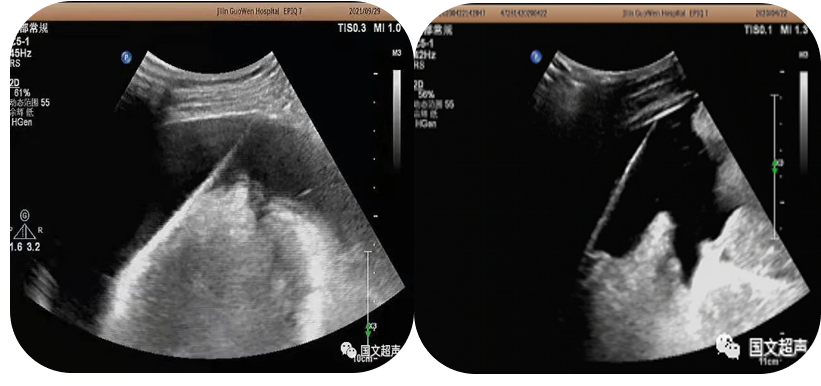

2.超声引导下置管引流

超声实时引导下将引流管放置在胸腹腔积液,脏器及间隙脓肿内抽取积液减轻症状,亦可将药物注入到某些特定部位从而达到治疗效果。

logiq e怎么读超声影像 | 国文医院引进GE LOGIQ E11全“芯”高端全身超声_https://www.jmylbn.com_新闻资讯_第9张 经皮脓肿穿刺引流

心包积液穿刺引流/腹腔积液穿刺引流